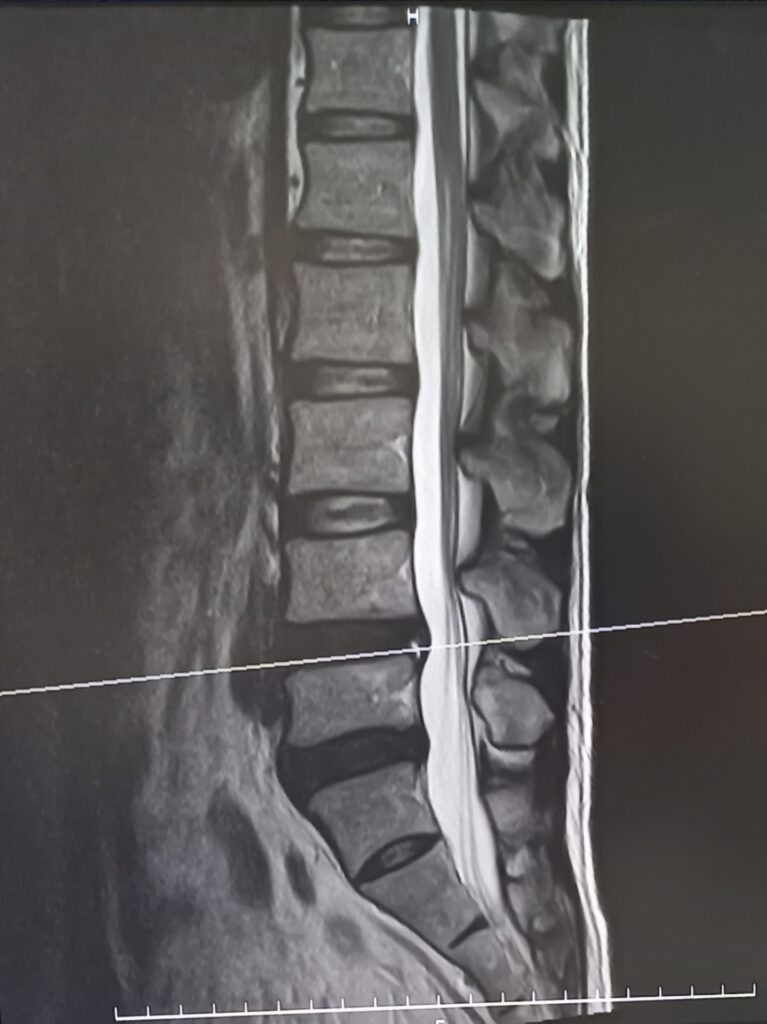

■ 検査でわかるのは「形の異常」📸

レントゲンやMRIでわかるのは、

- 骨の変形

- ヘルニア

- 明らかな損傷

- 炎症や腫れ

つまり、目に見える構造的な異常です。

これはとても大切な検査ですが、